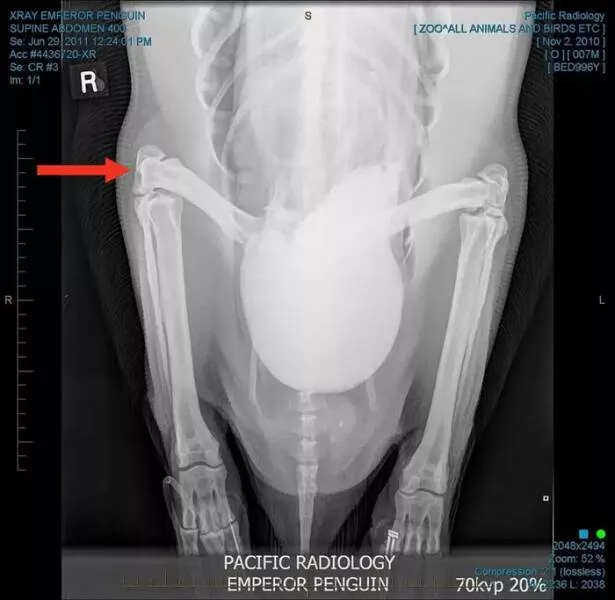

#17 Penguins have knees!